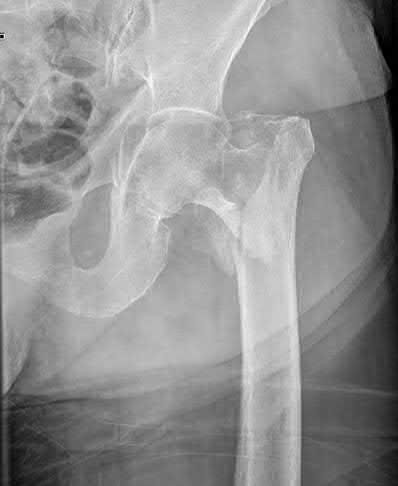

A 12-year-old obese boy presents with vague left thigh and knee pain. He is diagnosed with a Slipped Capital Femoral Epiphysis (SCFE) as seen in similar clinical scenarios.

During percutaneous in-situ fixation, unrecognized penetration of the guide wire into the hip joint occurs. What is the most likely specific complication resulting from this technical error?

Explanation

Chondrolysis is a severe complication of SCFE characterized by rapid destruction of the articular cartilage. While it can occur idiopathically, its most established iatrogenic cause is unrecognized intra-articular hardware penetration. The 'approach-withdraw' fluoroscopic technique is required during pinning to assure pins are entirely intraosseous. Avascular necrosis (AVN) is usually due to damage to the epiphyseal blood supply (retinacular vessels) secondary to the initial displacement, forceful closed reduction, or posterosuperior pin placement.